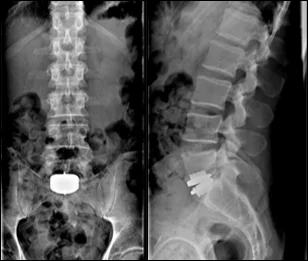

Before & After Clinical Gallery

We showcase real patient cases (with consent), including:

• Pre- and Post-operative MRIs and X-rays

• Disc Herniations, Stenosis, and Spondylolisthesis cases

• Visible improvement in alignment and decompression

Before

After